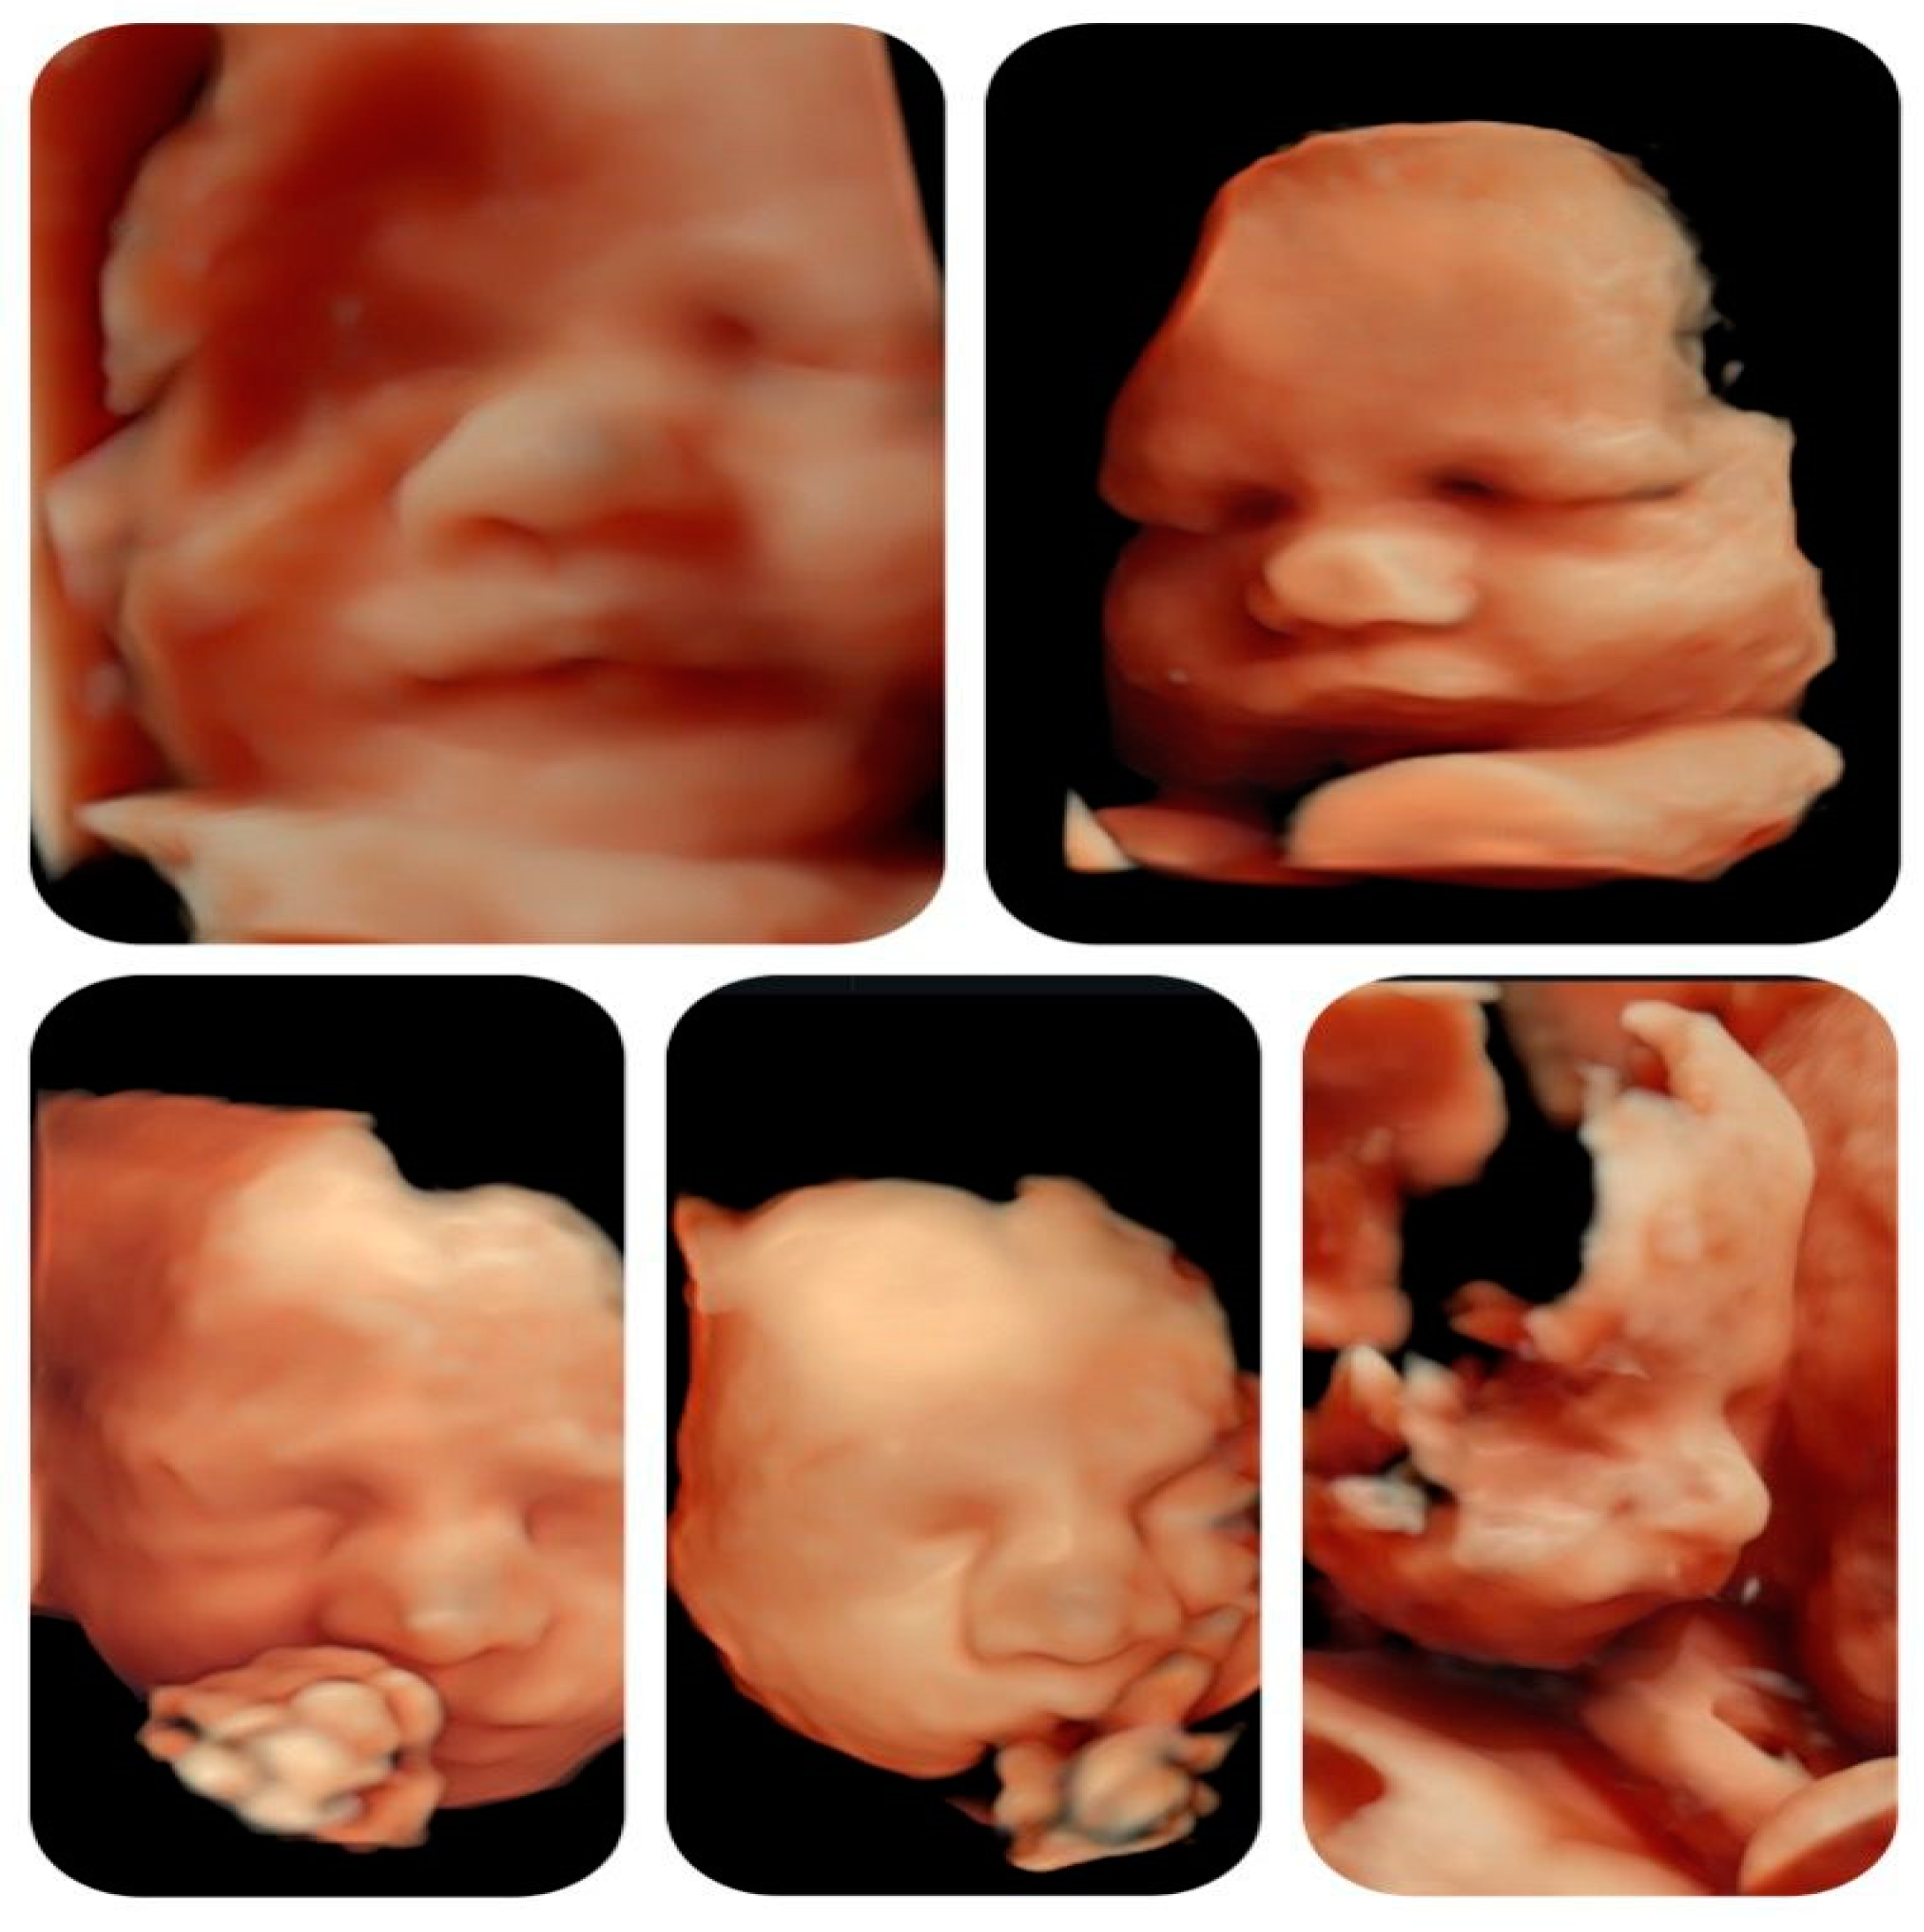

In the second half of gestation, we observed an enlarged cavum septum pellucidum (CSP) and polyhydramnios. Extracardiac findings included typical facial features, such as a bulbous nose (

Figure 4).

Although it is known that facial dysmorphism is typical in infants with this microdeletion, the prenatal ultrasound signs are not specific and can be subjective. The 3D reconstruction of fetal did not show any particular features throughout the gestation (

Figure 5).